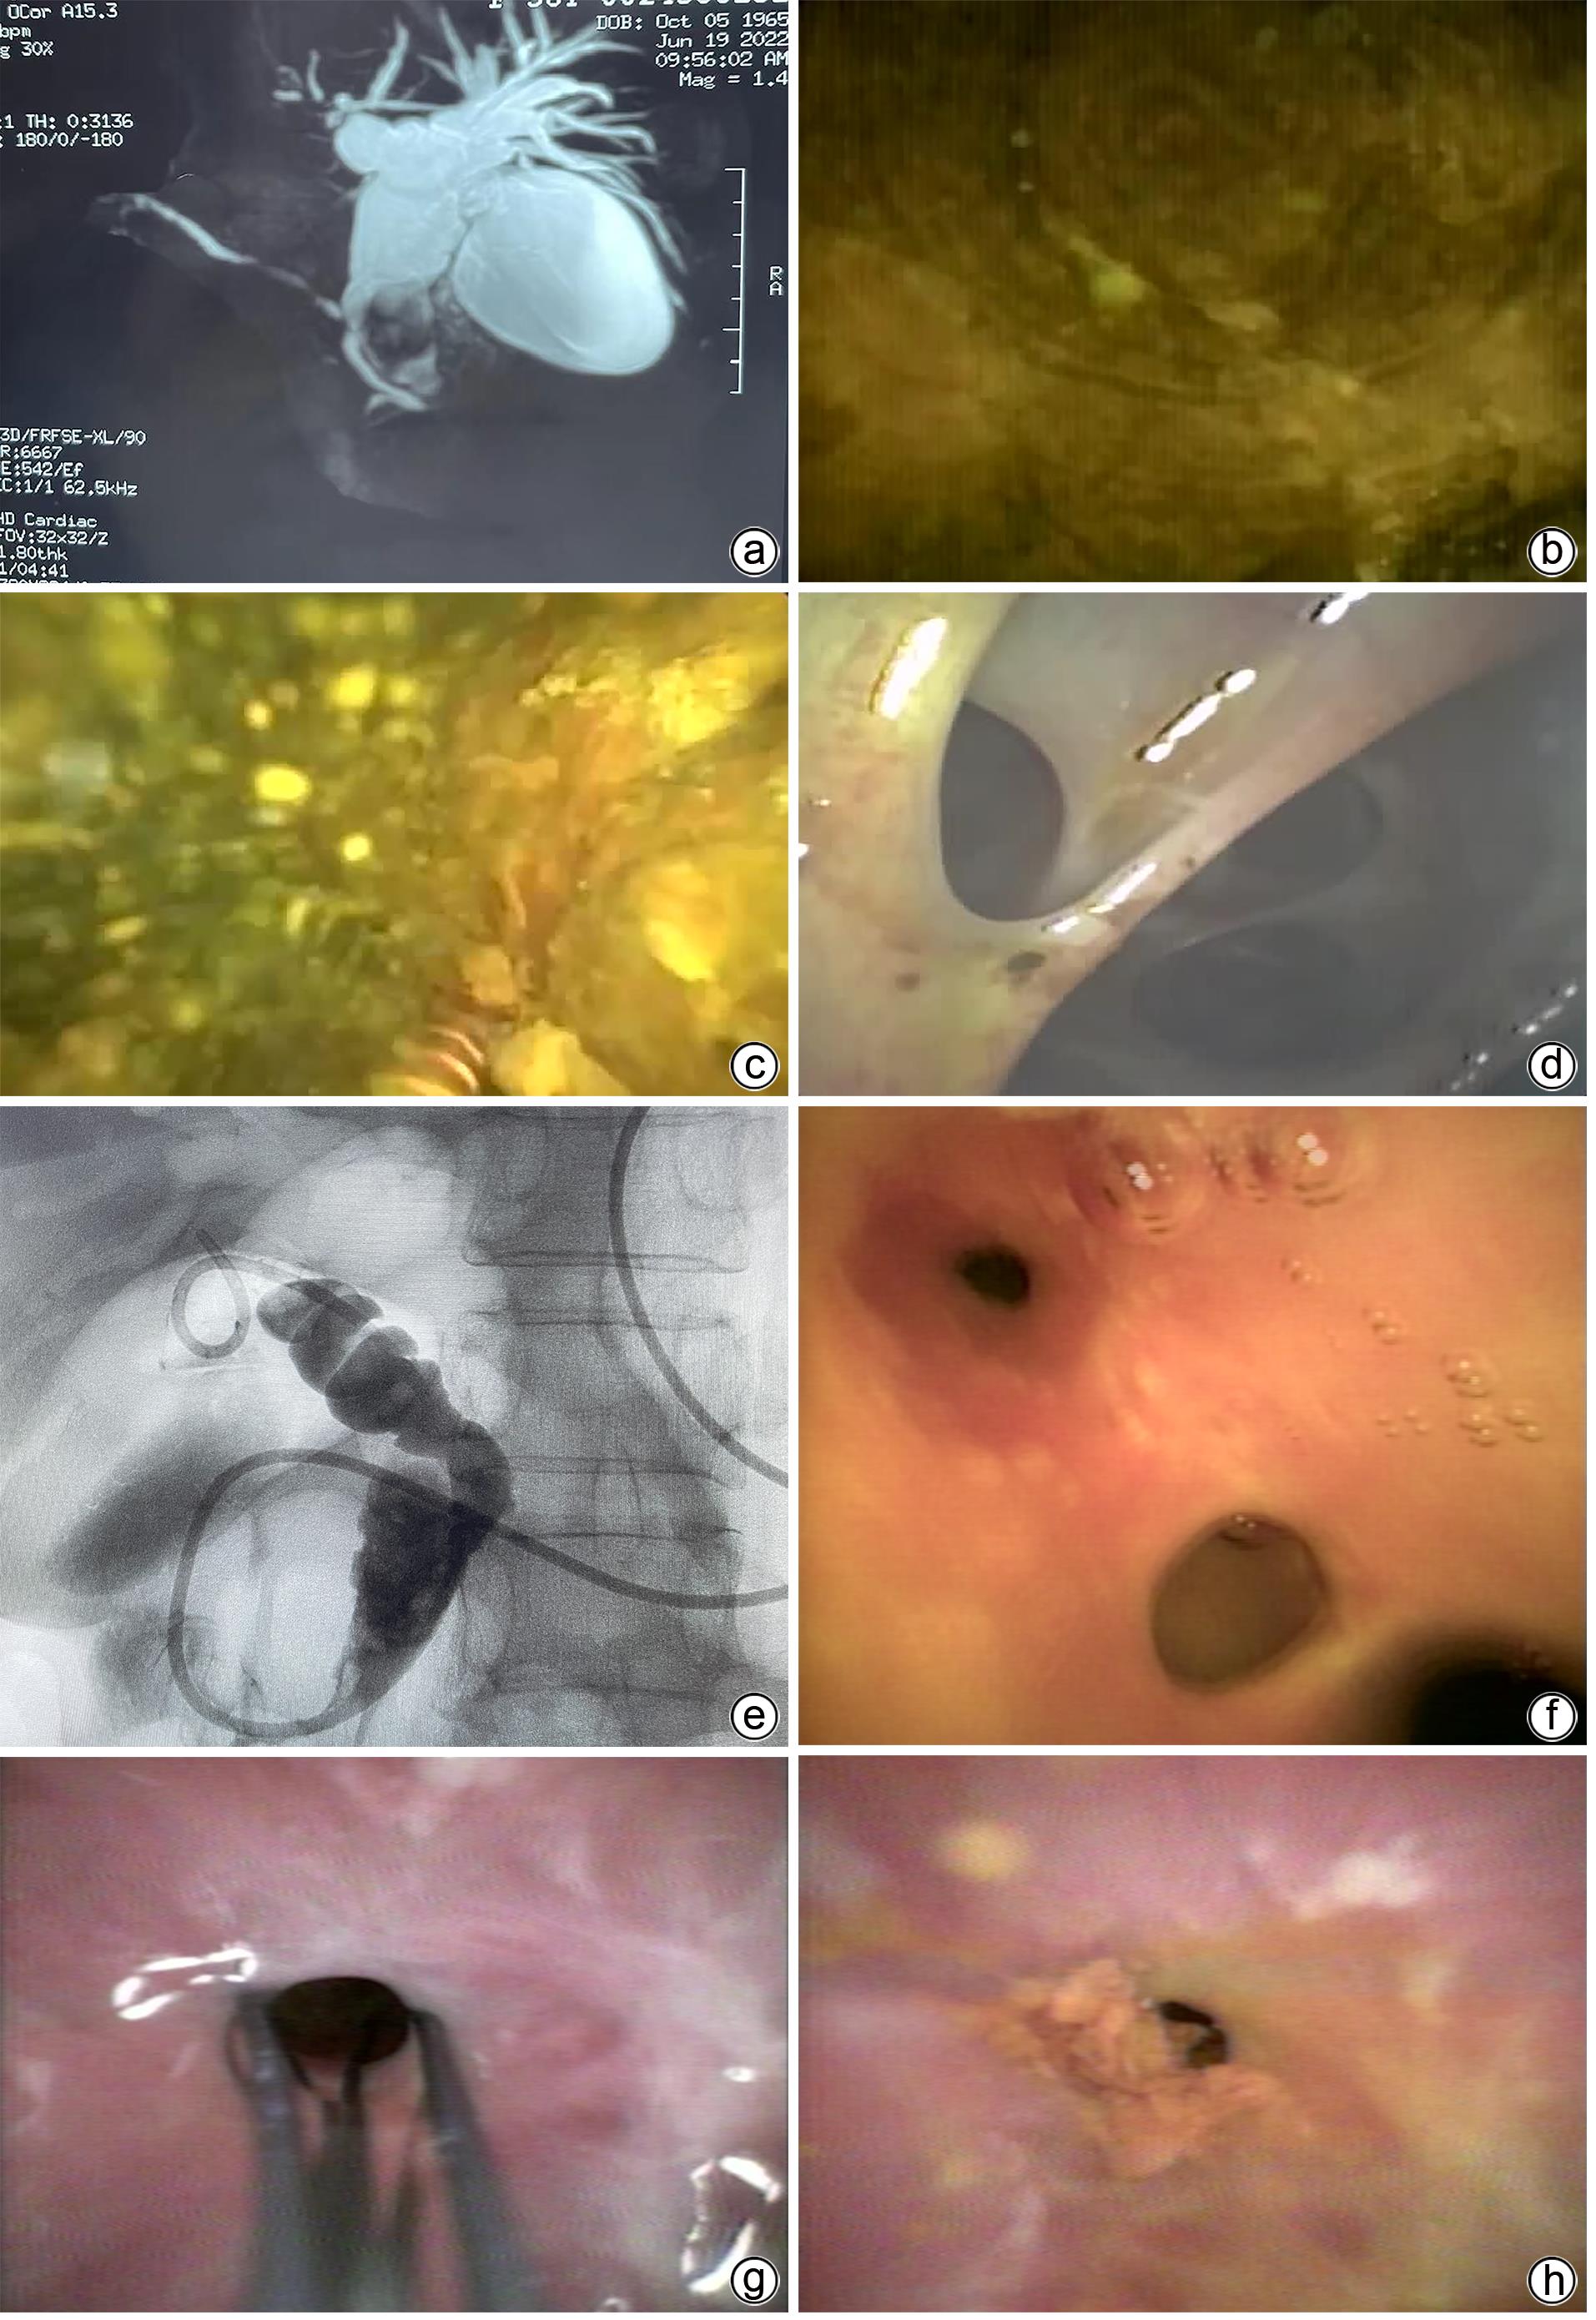

内镜逆行胰胆管造影联合eyeMax胆胰成像系统直视下液电碎石治疗困难胆管结石效果观察

摘要(1313) HTML (351) PDF (807KB)(127)

摘要:

目的  探讨内镜逆行胰胆管造影(ERCP)联合eyeMax胆胰成像系统直视下应用液电碎石技术治疗困难胆管结石的安全性及有效性。  方法  回顾性分析2022年5月—11月吉林市人民医院消化内科行ERCP联合eyeMax胆胰成像系统直视下应用液电碎石技术治疗困难胆管结石12例患者的临床资料,观察碎石、取石的临床效果,评估术后并发症发生情况,以及手术操作时间。  结果  12例患者中,11例(91.67%)患者直视液电碎石成功,9例(75.00%)一次性取石成功,11例(91.67%)达到结石完全清除,1例患者因多次胆道手术造成胆管多处狭窄,直视下将狭窄处上方的Ⅱ级肝内胆管结石取出,但仍残留Ⅲ级肝内胆管结石,进而未能达到结石完全清除的效果;ERCP平均操作时间(91.3±26.2)min,其中能量碎石时间为(41.8±22.2)min;术后2例胆道感染,给予抗感染后好转;2例高淀粉酶血症,未予特殊处置;3例轻度胰腺炎,给予药物对症治疗后好转;无出血、穿孔等并发症。  结论  ERCP联合eyeMax胆胰成像系统直视下应用液电碎石技术治疗困难胆管结石安全、有效、可行。